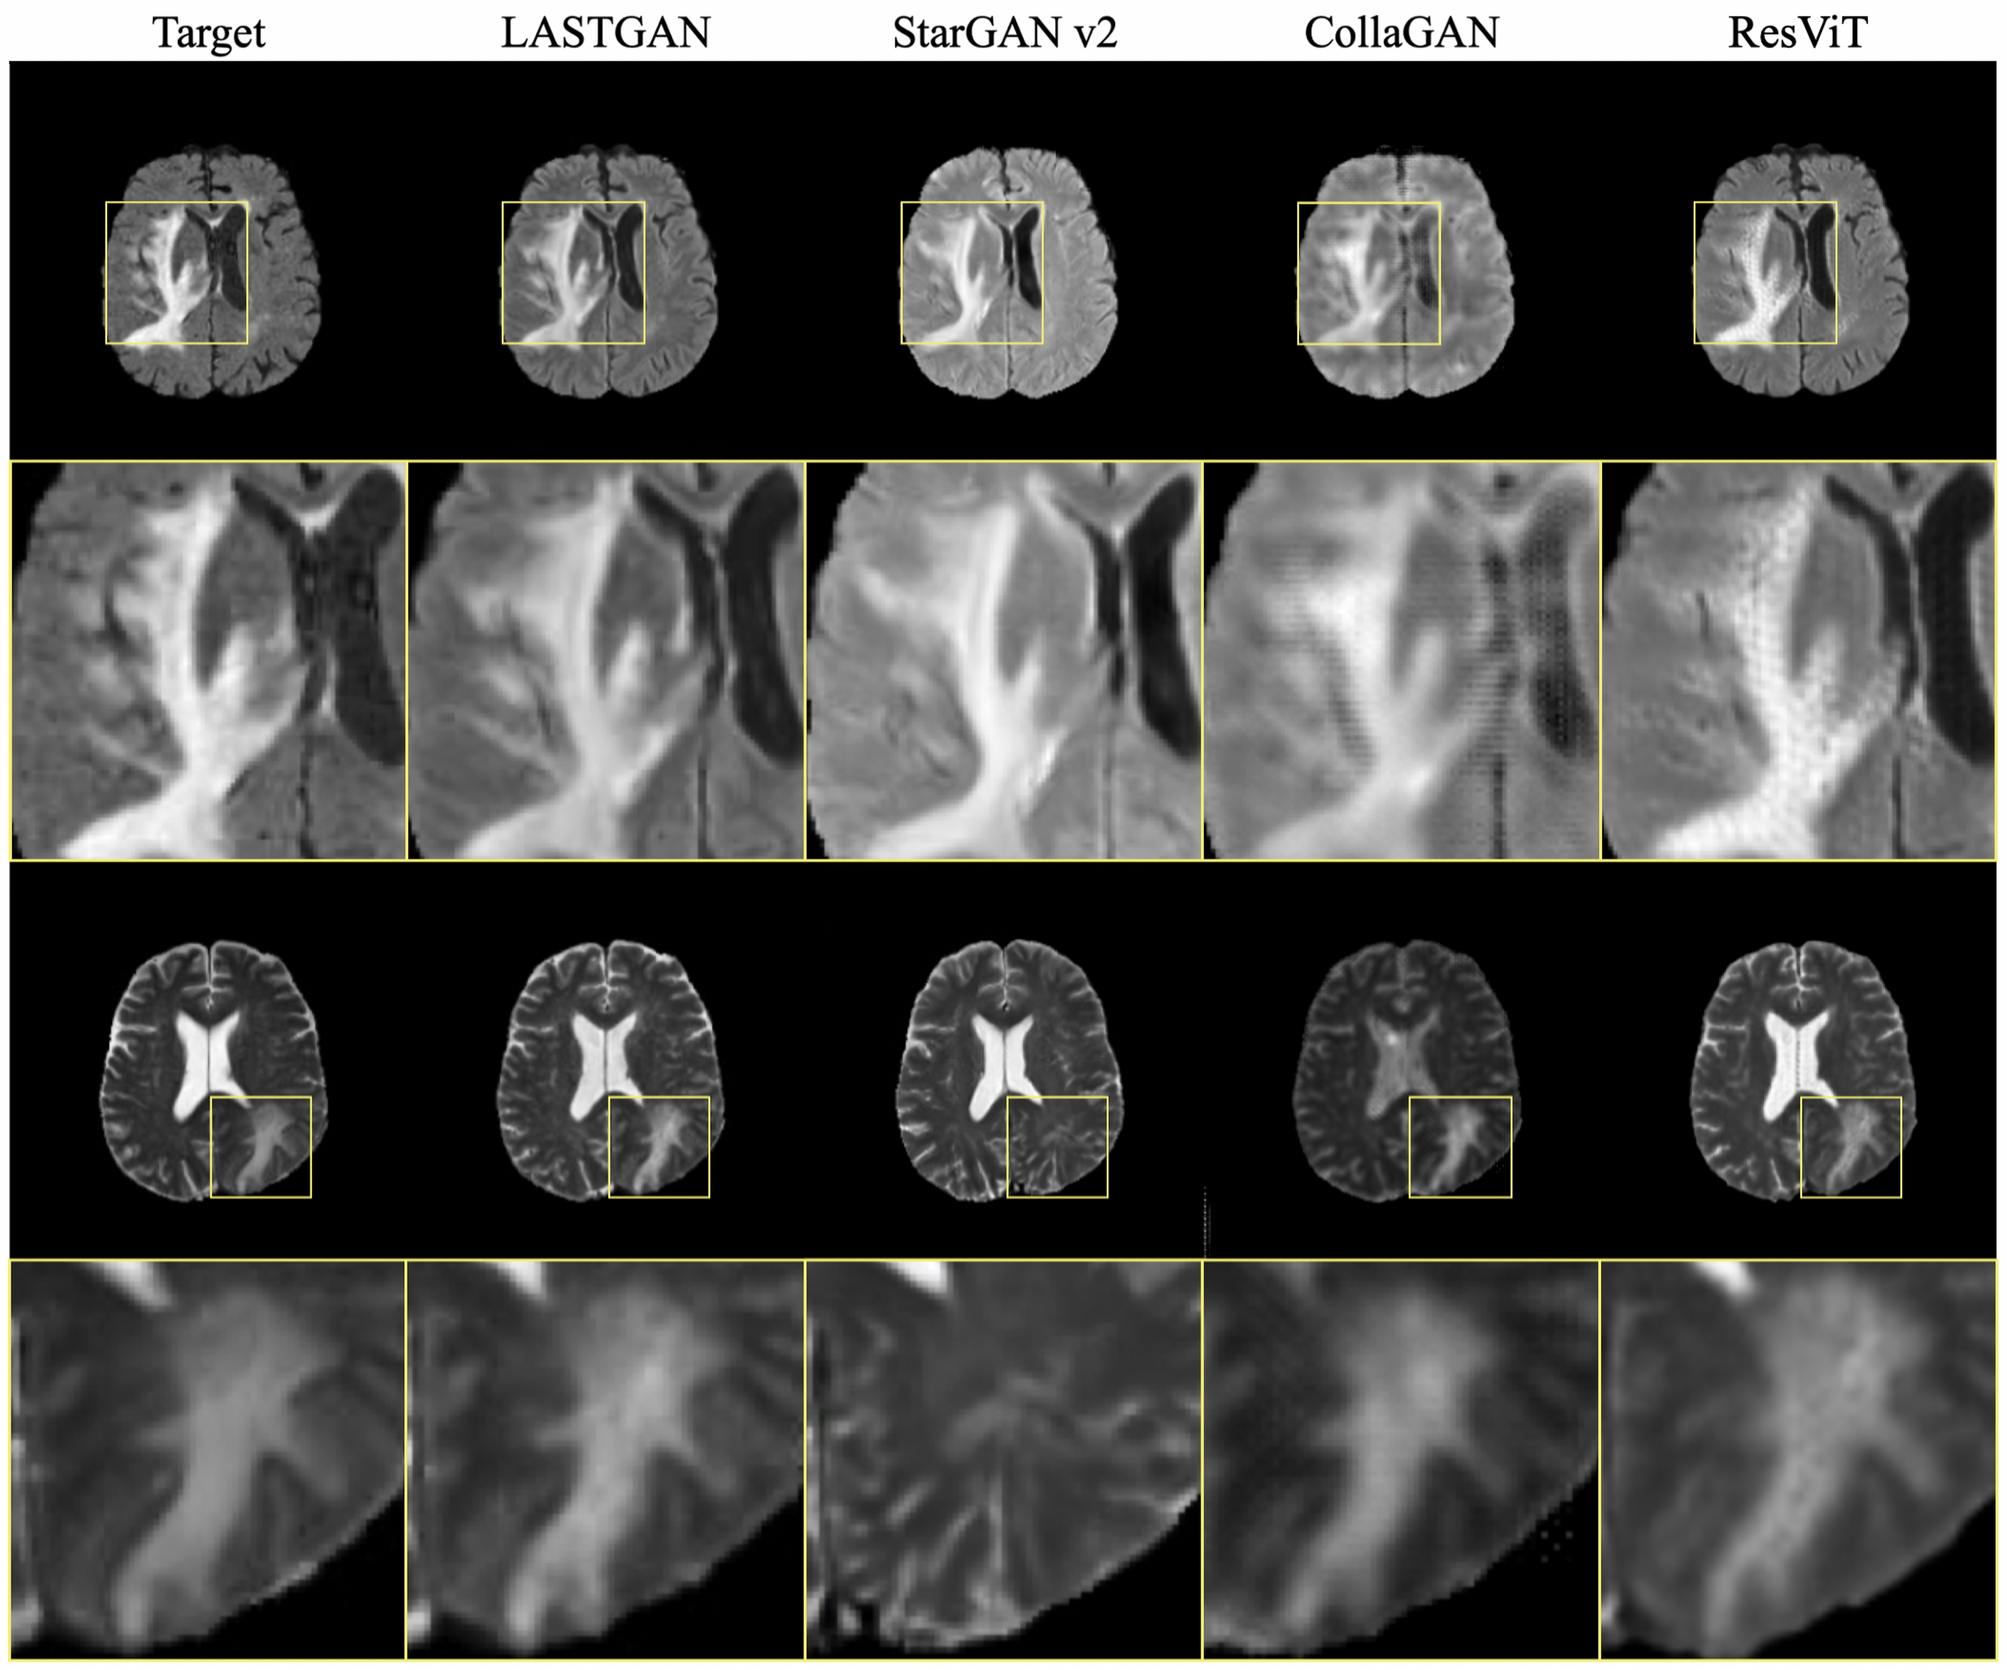

Enlarged images of the synthesized samples of LASTGAN, StarGAN v2, CollaGAN, and ResViT. The target images are shown in the left column for comparison.